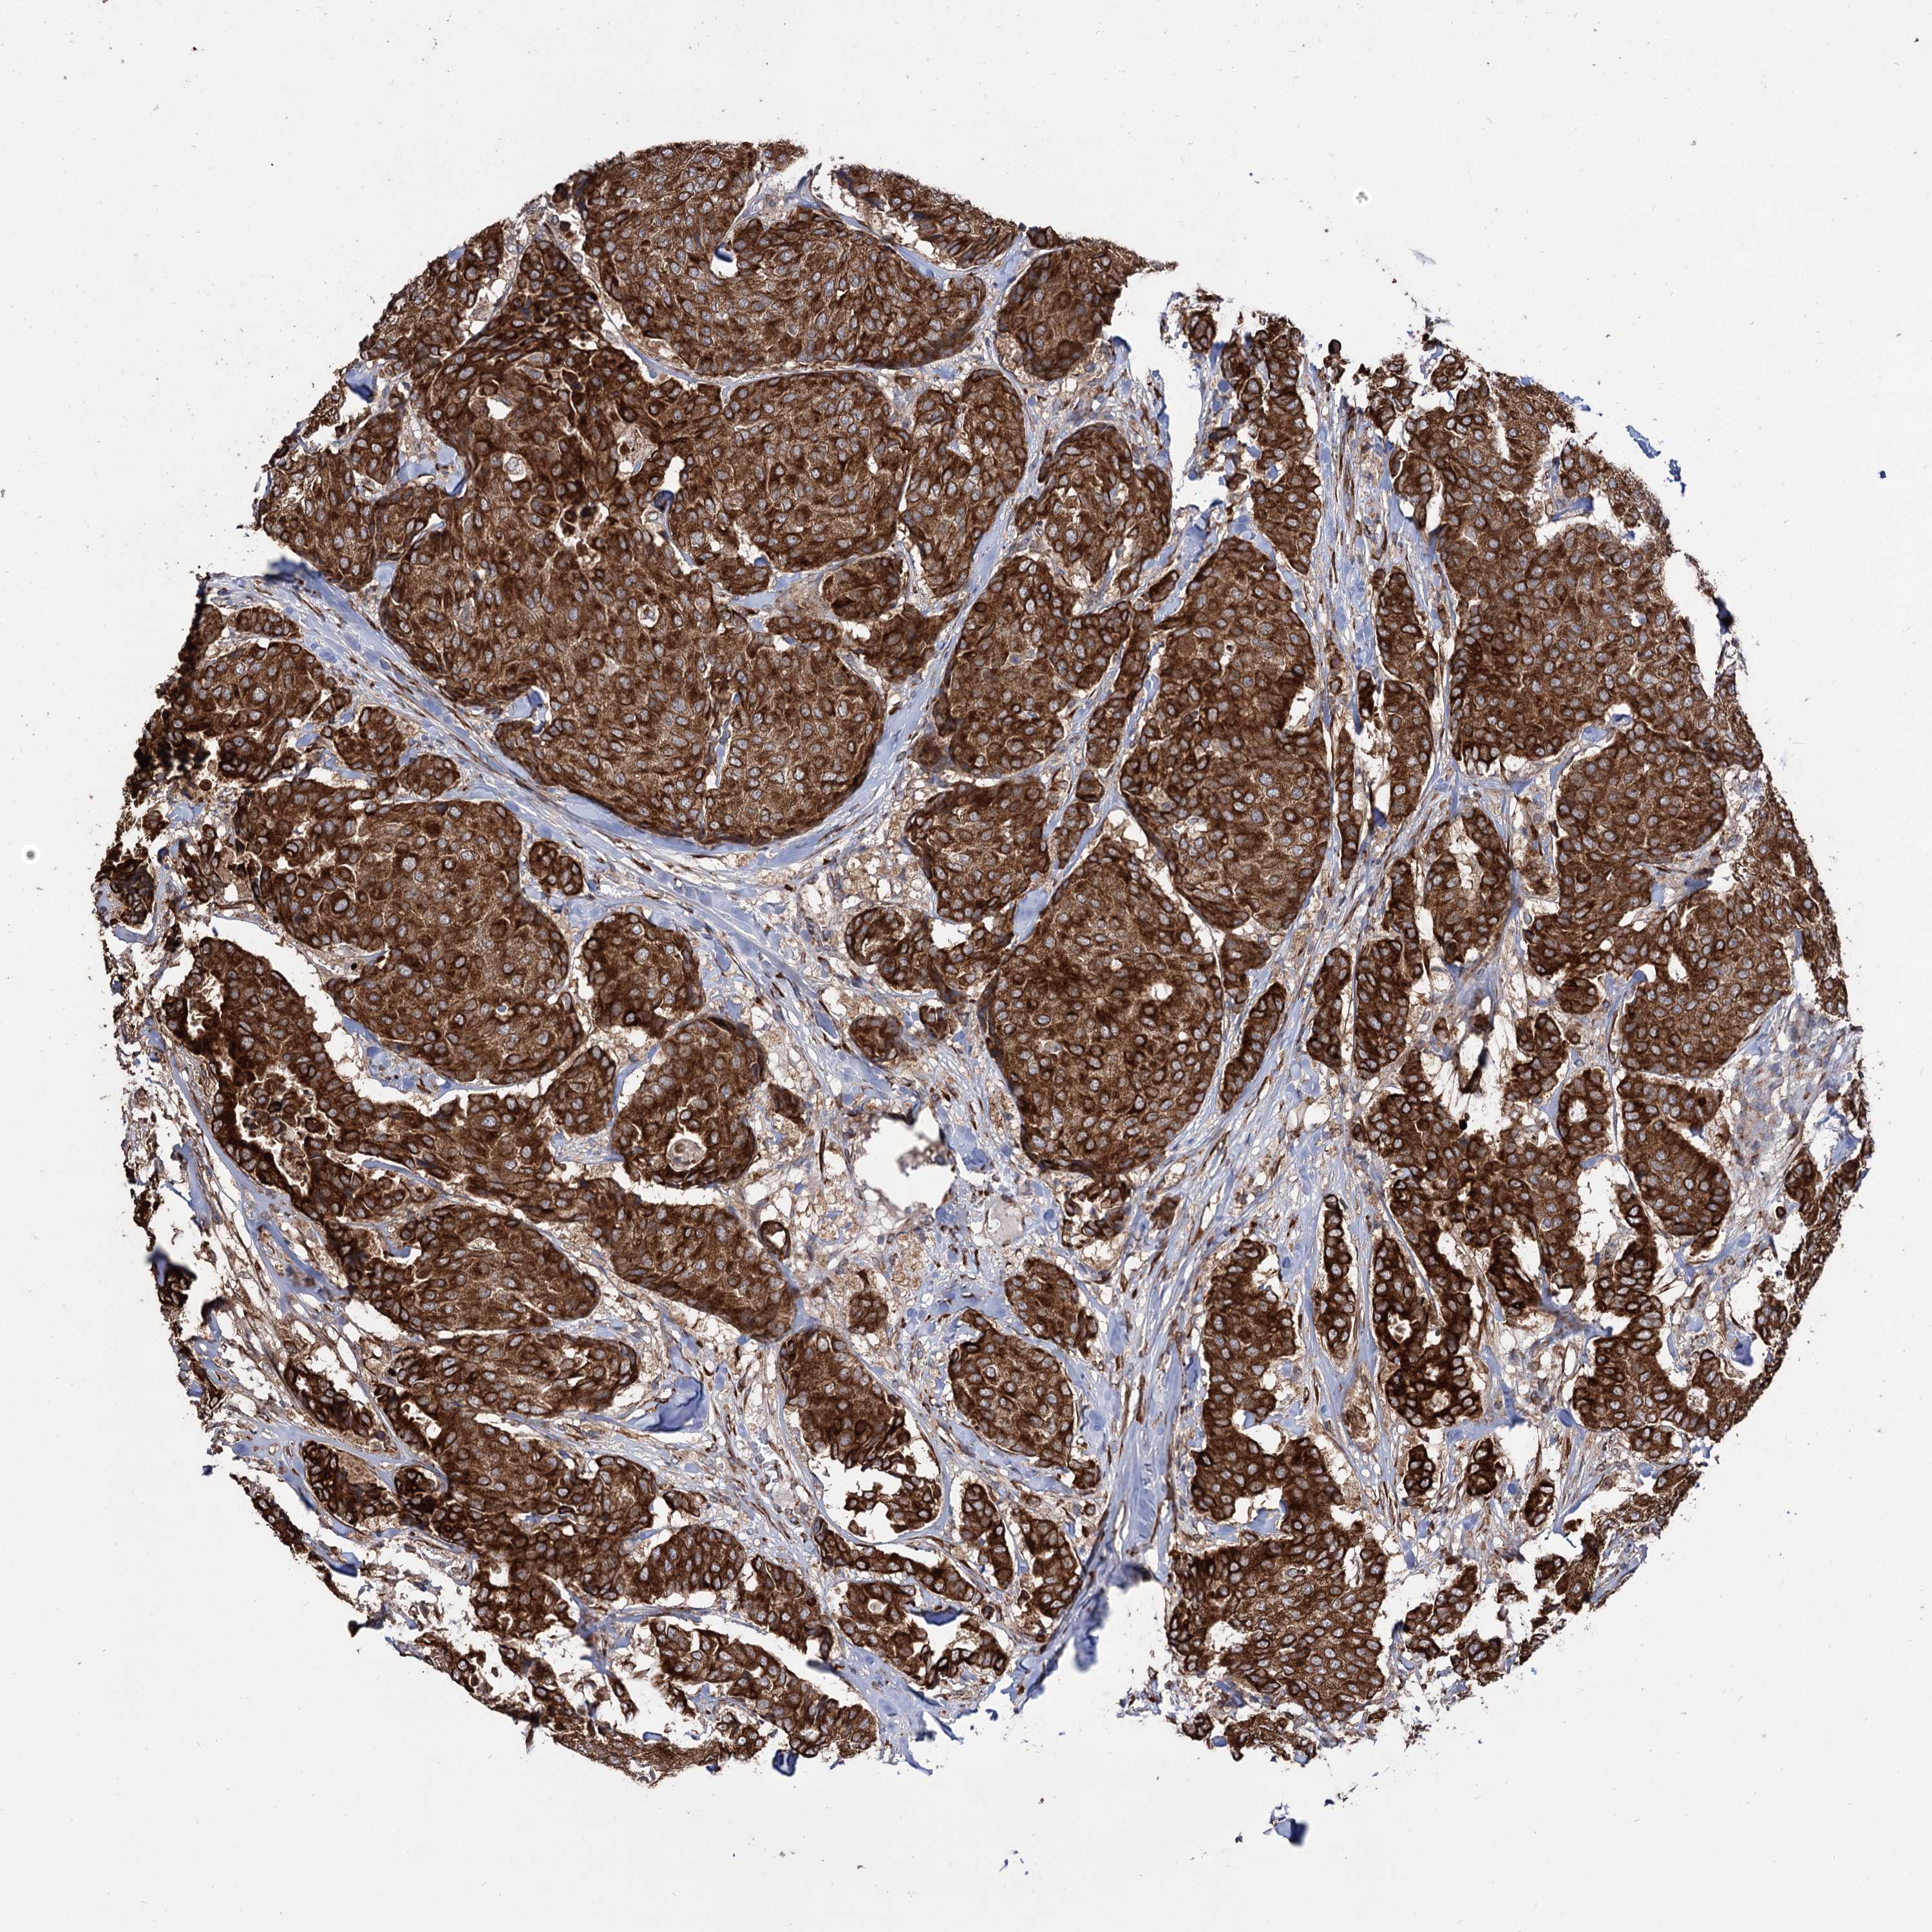

CANCER BREAST CANCER Show tissue menu

BRCA TCGA BRCA VALIDATION PROTEIN EXPRESSION